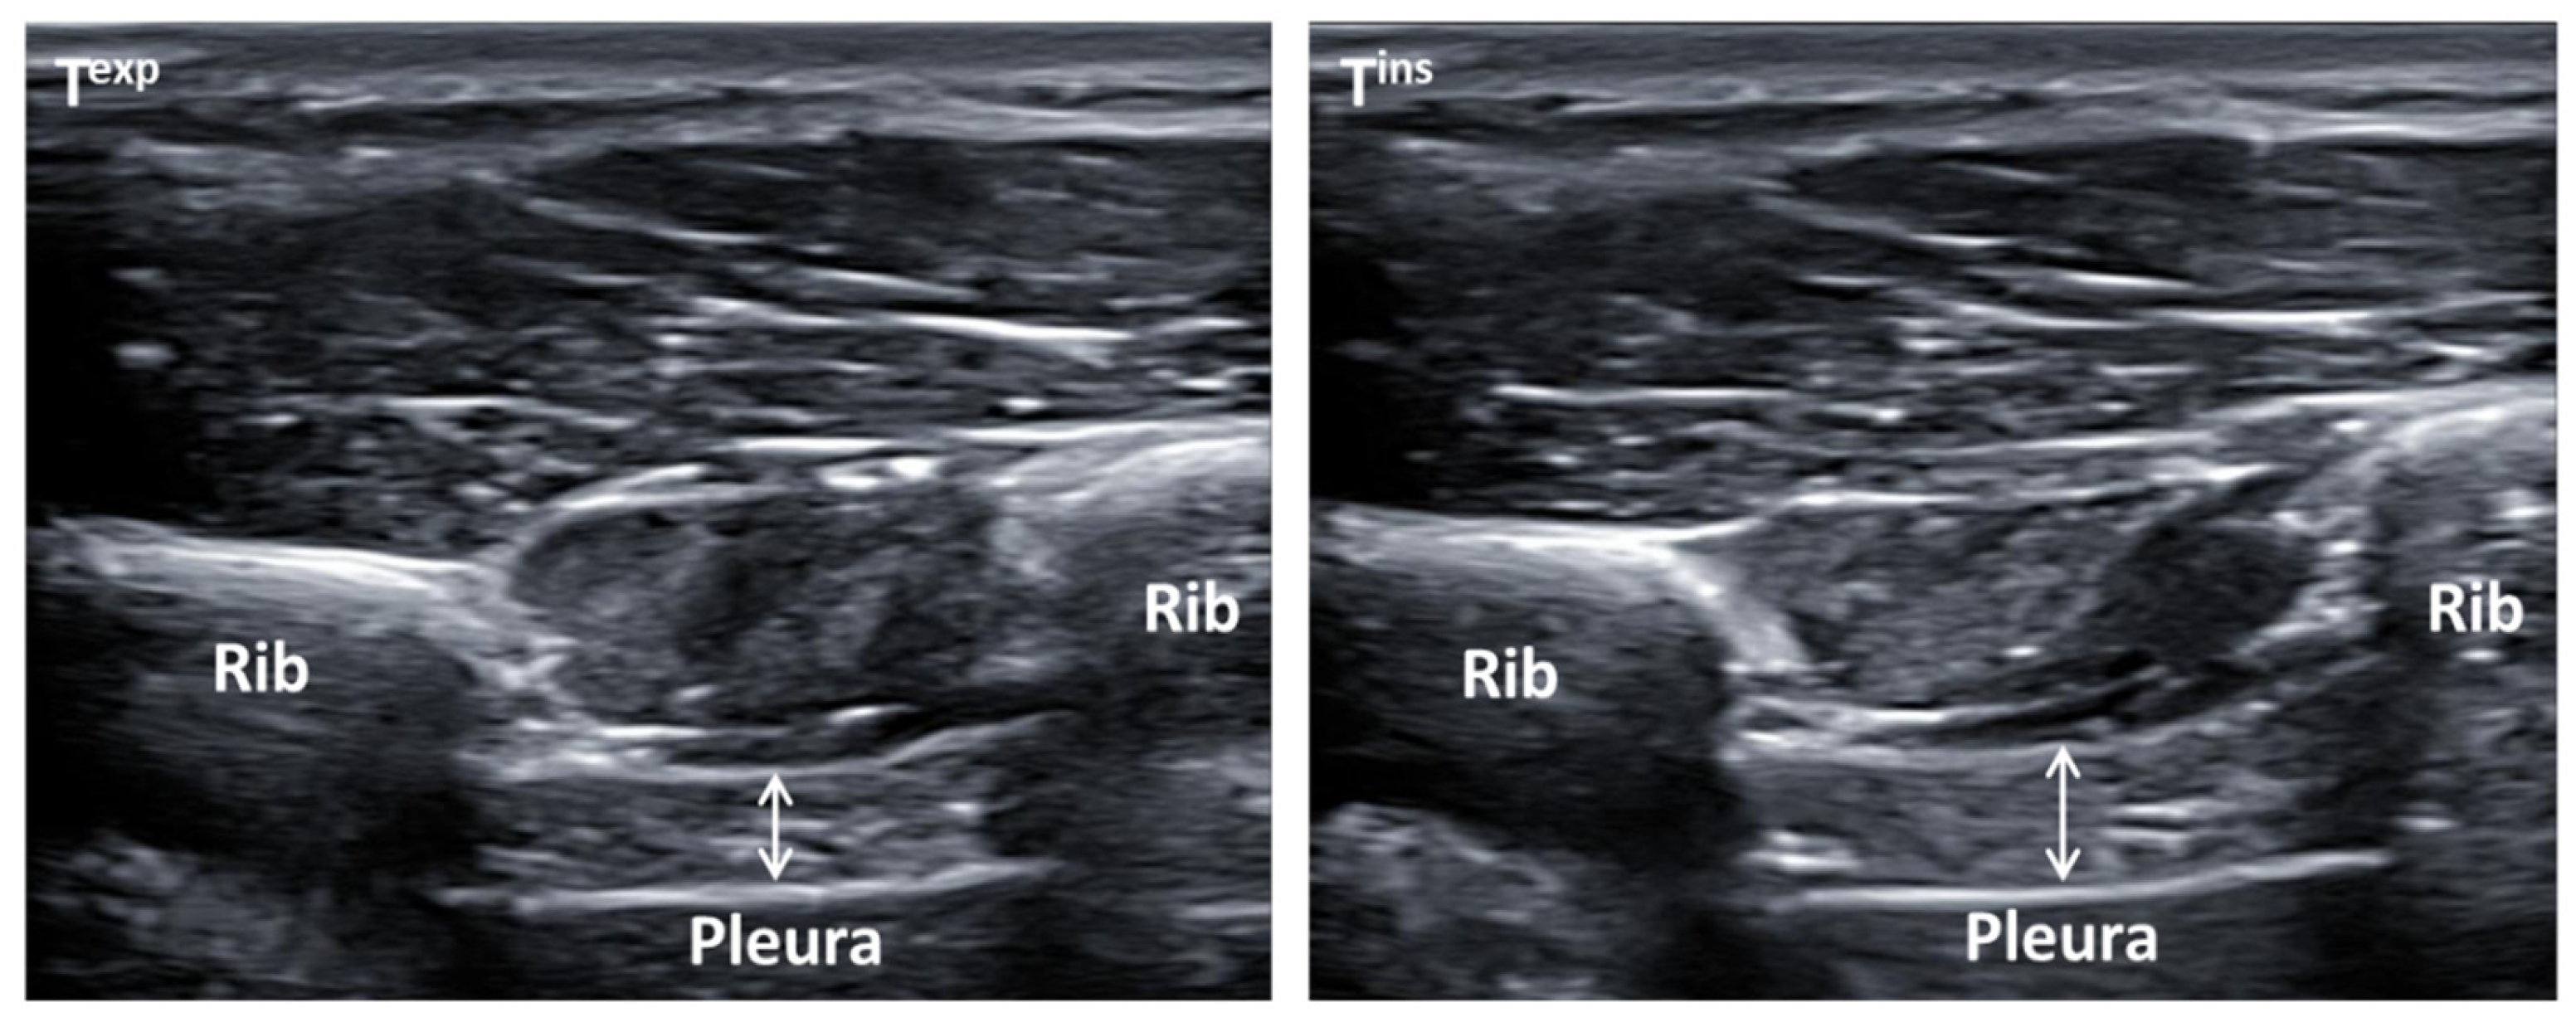

Ultrasound measurements were performed at transcostal location for both right and left hemi-diaphragm thickness (cm) at maximum inspiration (Tins) and expiration (Texp), and calculating their differences (Tins-exp) during normal breathing. Two high-quality ultrasound devices were used to determine all ultrasound measurements and images (Ecube-i7; Alpinion from Medical Systems; Seoul, Korea). All images were taken using 2 linear probes (L3_12T-types; 34 mm field of view; with 128 elements), with a frequency from 8 MHz to 12.0 MHz and a footprint of 45 mm. These measurements were performed at supine position by B-mode ultrasound imaging with a prefixed preset including 3 cm deep, 12 MHz frequency, 64 points gain, 64 points dynamic range, and 1 focus located at 2 cm depth [,,,]. All ultrasound images were taken in grayscale and converted in the format of Digital Imaging and Communications in Medicine (DICOM), calibrated by the 2.0 v-ImageJ software (U.S.-National Institutes of Health; Bethesda, MD, USA) to determine the thickness of both hemi-diaphragms [,,]. Furthermore, the linear probes were placed perpendicular to the last intercostal spaces following the mid-axillary line from the lower edge of the 11th rib to the upper edge of the 12th rib of the thorax region, permitting a correct diaphragm visualization under connective tissue of intercostal muscles during normal breathing activity (Figure 1). A total of 3 repeated measures were carried out to measure both right and left hemi-diaphragms thickness at Tins, Texp, and Tins-exp, using 3 images for each parameter, which showed a reduction in errors of measurement []. Both hemi-diaphragms’ thickness measurements were carried out by placing each electronic caliper inside of the upper and lower hyper-echogenic lines from the connective tissue around the diaphragm muscle, locating the thickness measurements at the center of the intercostal space. A total of 3 repeated measurements were applied to calculate the final mean. Both right and left probes’ fixation was performed by the bilateral orthotic device according to the manual measurement errors reductions, and separate unilateral measurements were carried out according to the better reliability parameters, showing excellent reliability to determine ultrasound thickness measures of the diaphragm muscle during normal breathing, with intraclass correlation coefficients (ICC) of 0.852–0.996, standard errors of measurement (SEM) of 0.0002–0.054 cm, and minimum detectable changes (MDC) of 0.002–0.072 cm, avoiding systematic measurement errors [,].

Figure 1.

Ultrasonography images by B-mode of the diaphragm thickness that illustrated the last intercostal spaces coinciding with the mid-axillary line between the lower edge of the 11th rib and the upper edge of the 11th rib of the thorax region. (Texp) Diaphragm thickness measurements were determined by the white arrow at maximum expiration (Texp) during normal breathing placed at the left side of this figure. (Tins) Diaphragm thickness measurements were determined by the white arrow at maximum inspiration (Tins) during normal breathing placed at the right side of this figure.